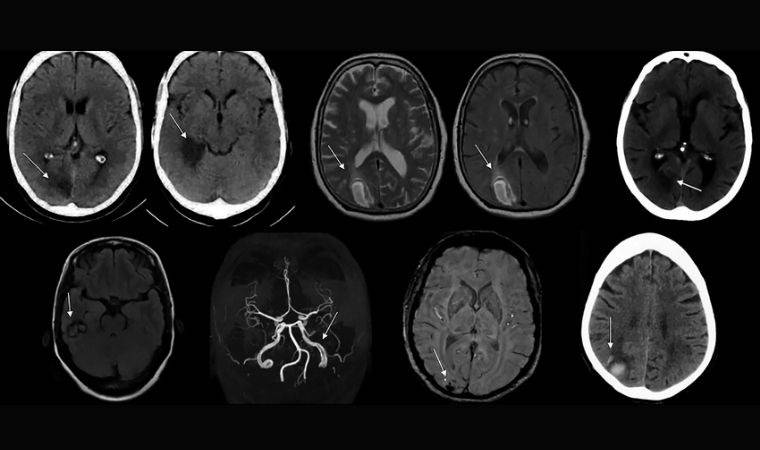

Çeşitli beyin bölgelerinde AIWS’ye bağlı beyin hasarı da rapor edilebiliyor. Çalışmanın yazarları, bunu anlamlandırmak için, tamamı daha önce tıbbi literatürde belgelenen vakalardan AIWS’li 37 kişinin beyin taramaları üzerinde lezyon ağı haritalaması adı verilen bir teknik uyguladılar.

Ekip, bu taramaları 1.000 sağlıklı kişiden ve 25 farklı nöropsikiyatrik bozuklukla ilişkili 1.073 lezyondan alınan verilerle karşılaştırdı. Birey bazında AIWS beyin lezyonlarının konumları farklılık gösterse de yüzde 85’inden fazlasının, sağ ekstrastriat vücut alanı (EBA) ve sol alt parietal lob (IPL) olmak üzere iki spesifik merkeze bağlı olduğunu keşfedildi.

Sağ EBA, beynin daha büyük görsel işleme alanının bir parçasıdır ve bir bedeni veya onun parçalarını gözlemlediğimizde etkinleşirken, bir şeyin boyutunu belirlemeye çalıştığımızda ise sol IPL devreye giriyor. Bu yüzden bu iki bölgenin, insanların vücut parçalarının anormal derecede küçük veya büyük görünmesine neden olan bir bozuklukla ilgili olması oldukça mantıklı görülebilir.